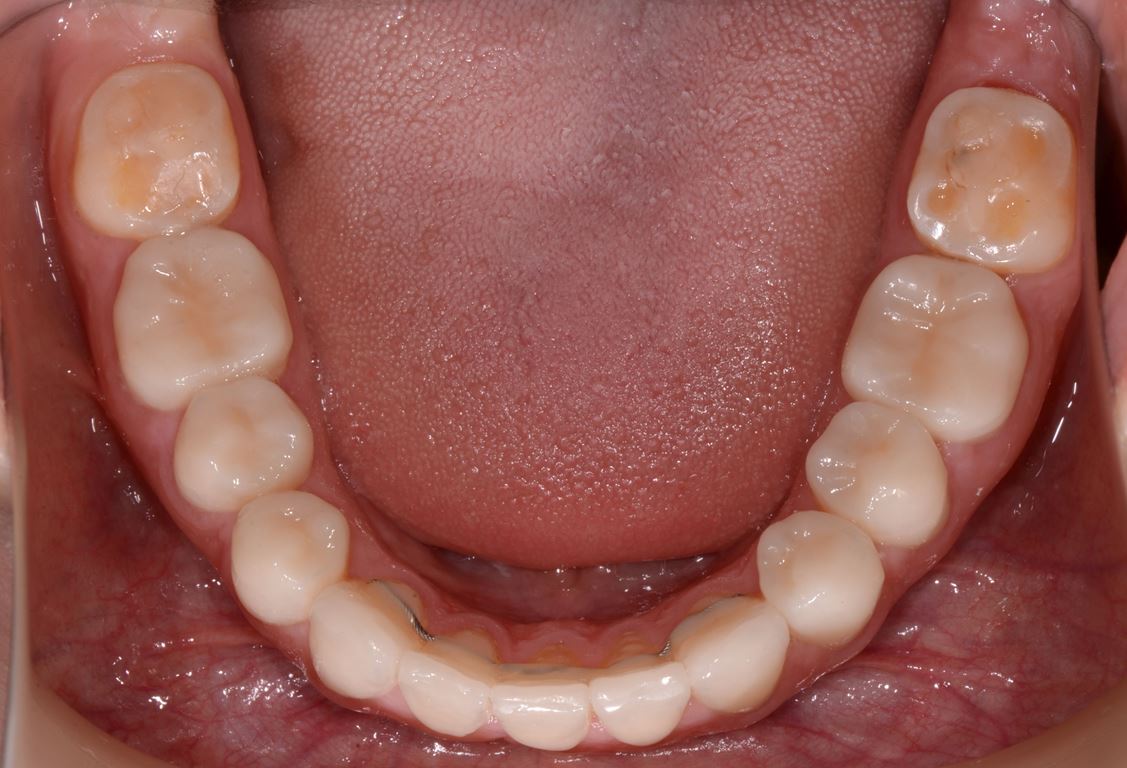

W pierwszym etapie diagnostycznym wykonano zdjęcia zewnątrz- i wewnątrzustne (ryc. 1-12).

Bezpośrednio po usunięciu zębów rozpoczęto leczenie ortodontyczne, które trwało 15 miesięcy i pozwoliło na uzyskanie zaplanowanych wcześniej pozycji zębów (ryc. 22-24).